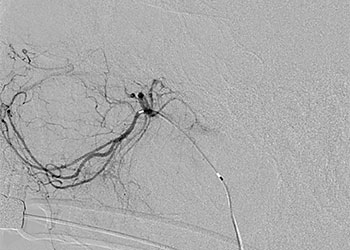

Endovascular:

CME:

Symptomatic Near-Occlusion of the Carotid Artery

Author: Jonathan L. Brisman M.D., F.A.C.S., Read More!